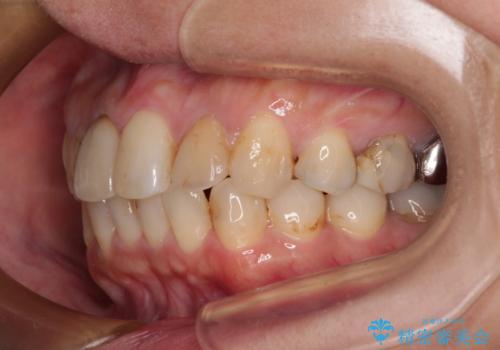

- 上下前歯のデコボコを気にして来院された患者様です。

歯列としては、ワイヤー装置でもインビザラインでも、どちらでも対応可能でしたが、処置されている歯が多く、ワイヤー装置を装着するためには処置歯のやり直しが必要な状態でした。

インビザラインでもアタッチメントを装着できないという同様のデメリットがありますが、比較的矯正治療を行いやすい歯列であったので、インビザラインによる矯正治療を行うこととしました。